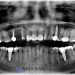

Zygomatic dental implants are used when the upper jawbone has resorbed to the point where conventional implants cannot be placed. Instead of anchoring in the weakened maxilla, these implants extend into the zygomatic bone. The proximity to the sinus and orbital structures means that CBCT scans with zygomatic dental implants are not optional; they are a fundamental requirement for safe and successful treatment. CBCT enables the surgeon to assess the location and shape of the sinus cavity, measure the thickness and quality of the zygomatic bone, and choose the ideal implant length and angle.

Before surgery, the CBCT data is imported into advanced digital planning software. This allows the surgeon to virtually position implants and simulate the procedure. In CBCT scans with zygomatic dental implants, every millimeter counts. Virtual planning ensures that each implant enters and exits the bone at exactly the right point, avoiding nerves and vital spaces. This planning stage supports greater precision during surgery and reduces unnecessary guesswork.

Safety is one of the greatest advantages of using CBCT scans with zygomatic dental implants. Because these implants are placed near the sinus and beneath the eye socket, misjudgment in angulation or depth can lead to complications. CBCT scans provide the surgeon with accurate three-dimensional knowledge of the patient’s anatomy so critical structures can be clearly avoided. The technology also reveals any existing sinus disease, cysts, or anatomical variations that may alter the surgical approach.

By identifying anatomical risks in advance, CBCT scans with zygomatic dental implants significantly reduce the likelihood of perforation, nerve involvement, implant misplacement, or sinus complications. This allows the surgeon to enter the operating room with a clearly defined, patient-specific plan. The result is greater predictability, shorter surgical times, and higher success rates.